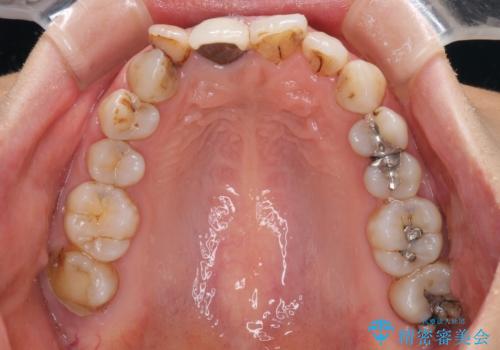

- 前歯の歯並びやむし歯治療の跡、奥歯の銀歯を気にして来院された患者様です。

インビザラインによる矯正治療の後に虫歯や銀歯をセラミックにて補綴することとしました。